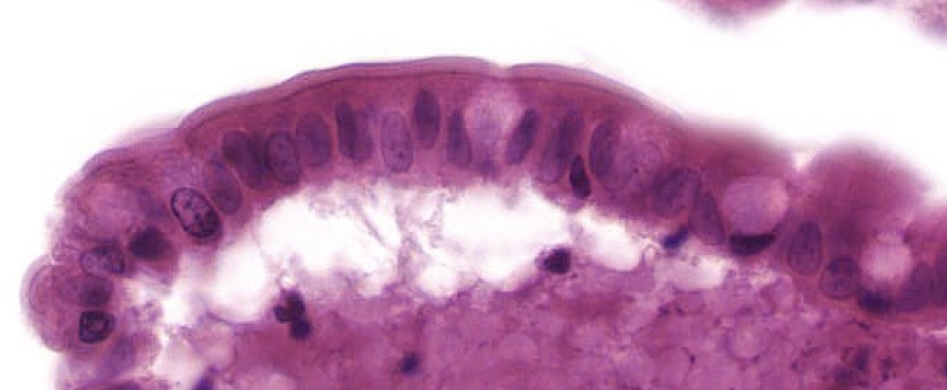

term image

Simple squamous

Strat squamous

Mesentery simple squamous cells

Simple squamous in bowman capsule kidney

Strat squamous in esophagus. Top cells are flat, living cells not keratinized